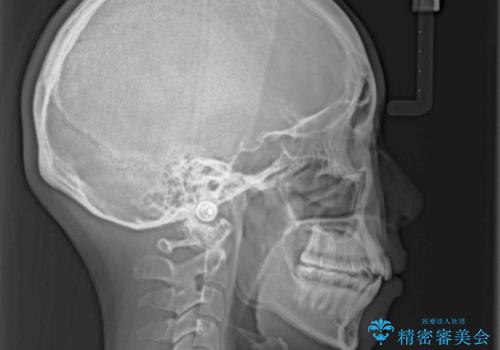

- 口元の突出感と口の閉じにくさを気にして来院された患者様です。

上下左右第一小臼歯4本を抜歯し、ワイヤー装置にて口元を引っ込めるよう矯正治療を行うこととしました。

口元の突出感が改善されてことで、下唇に引っかかっていた上顎前歯も気にならなくなりました。